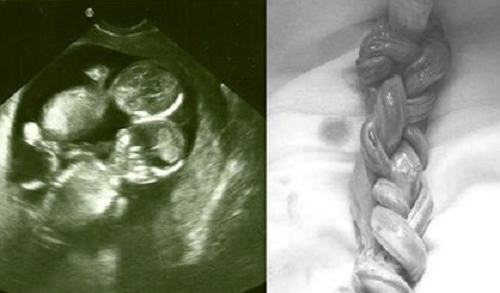

Sinh đôi và thân thể bị dính liền là tình trạng hiếm gặp ở các cặp song sinh. Và thông thường theo nhiều số liệu thì cơ hội sống sót của những cặp sinh đôi dính liền này là rất nhỏ. Tuy nhiên, trên thế giới vẫn có những cặp song sinh dính liền sống khỏe mạnh, thậm chí nổi tiếng và lập gia đình. Hãy cùng tìm hiểu những cặp song sinh dính liền dưới đây.

Cặp song sinh này chào đời vào năm 2006 tại Vancouver, Canada. Krista và Tatiana bị dính liền đầu, chung một phần não bộ và chia sẻ các tín hiệu não bộ, cảm xúc, suy nghĩ. Các nghiên cứu cũng xác nhận 2 người có thể trải nghiệm những gì người kia nhìn thấy.

Hai anh em có 4 tay 4 chân, tim và dạ dày riêng, nhưng chung bộ phận sinh dục. Toàn bộ hệ tiêu hóa như đường ruột, trực tràng do não của Donnie kiểm soát.